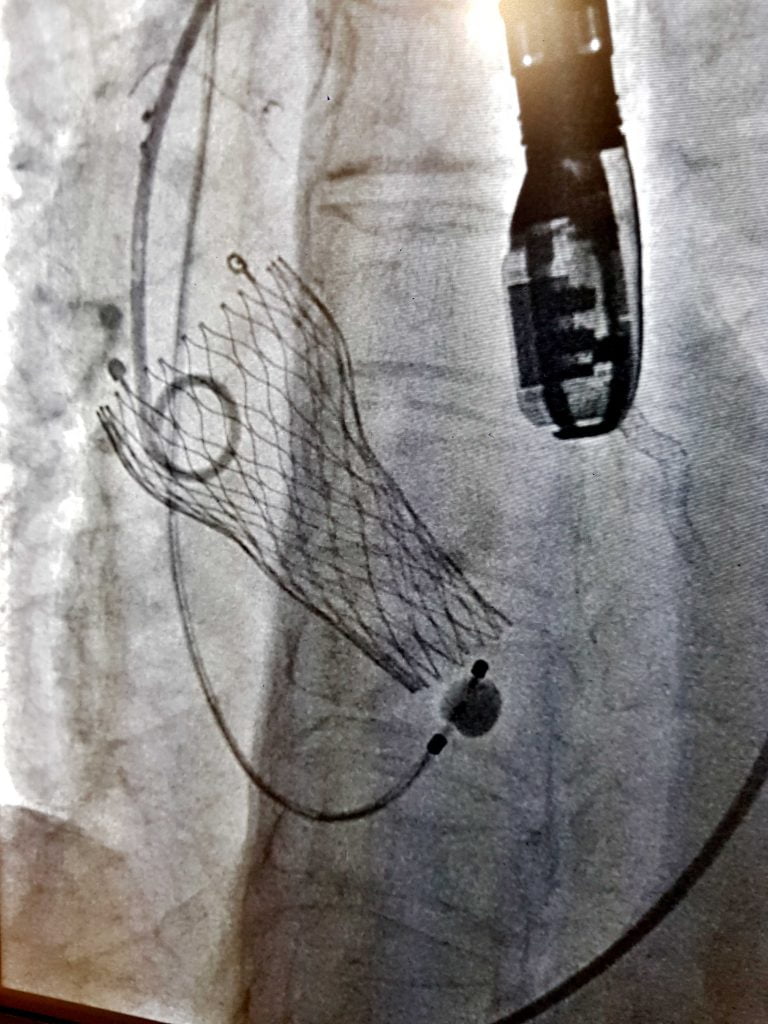

Bhubaneswar: The Kalinga Institute of Medical Sciences (KIMS) has successfully done the first case of Trans-catheter Aortic Valve Replacement (TAVR) on Wednesday.

The patient was evaluated by cardiologist and cardiac surgeon. She was found to be at high risk zone for carrying out of an open heart surgery on her. Therefore, she was advised to undergo Trans-catheter Aortic Valve Replacement (TAVR). Subsequently, the patient underwent TAVR.

TAVR or Trans-catheter Aortic Valve Implantation (TAVI) is a minimally invasive procedure that repairs the Aortic valve without removing the old, damaged valve.